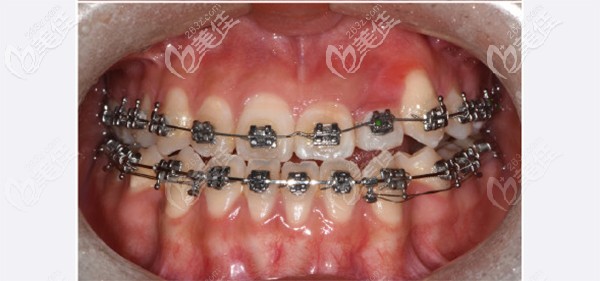

看到我娃牙齿居然比我想象中还要严峻,真心想要孩子把牙齿给做好,在和医生了解矫正方案后,我觉得还是做传统金属矫正吧,毕竟对于娃这种情况,我觉得采取保妥矫正比较合适。

戴上牙套后,给我心疼的,娃说牙疼,只能喝稀饭。

这是矫正2个月后,期间来院很多次,觉得现在能看出明显变化。